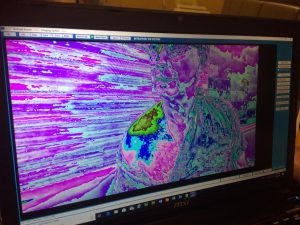

The pictures show the camera in operation, the before and after pictures.

Before ERIC mode  During ERIC mode (no radiation).

During ERIC mode (no radiation).

How Eric Works: ERIC works by capturing all the different frequencies of light being emitted by the human body. As an electron changes orbit it emits a photon of a certain colour, we can only see each other because we are constantly emitting phots that hit the retina of our eye which makes an image of you in our minds, thus we recognize each other. The camera works on these same principles, each element when it interacts with other elements produces photons equivalent to that reaction. When the elements react in our cells, our cells being like a miniature fusion reactor (thus 80% of our body is water to cool that reaction down) they emit photons of the equivalent frequency of the work being done within that cell. If the cell is contaminated with heavy metal ions or other physical metals. The body reacts with these to produce certain results. These results produce photons from the metals.

How Eric Was Invented: Each cell in the human body, plants and animals acts as a miniature fusion reactor, through an understanding of field and wave electronics we can see changes in our energetic, molecular and chemical processes. The reason I can see you is because you are constantly emitting light because of the changes that are taking place within you. With the advances in computers, electronics and optical devices we can now see the invisible world of energy. The once hidden world comes to life in vivid colour.